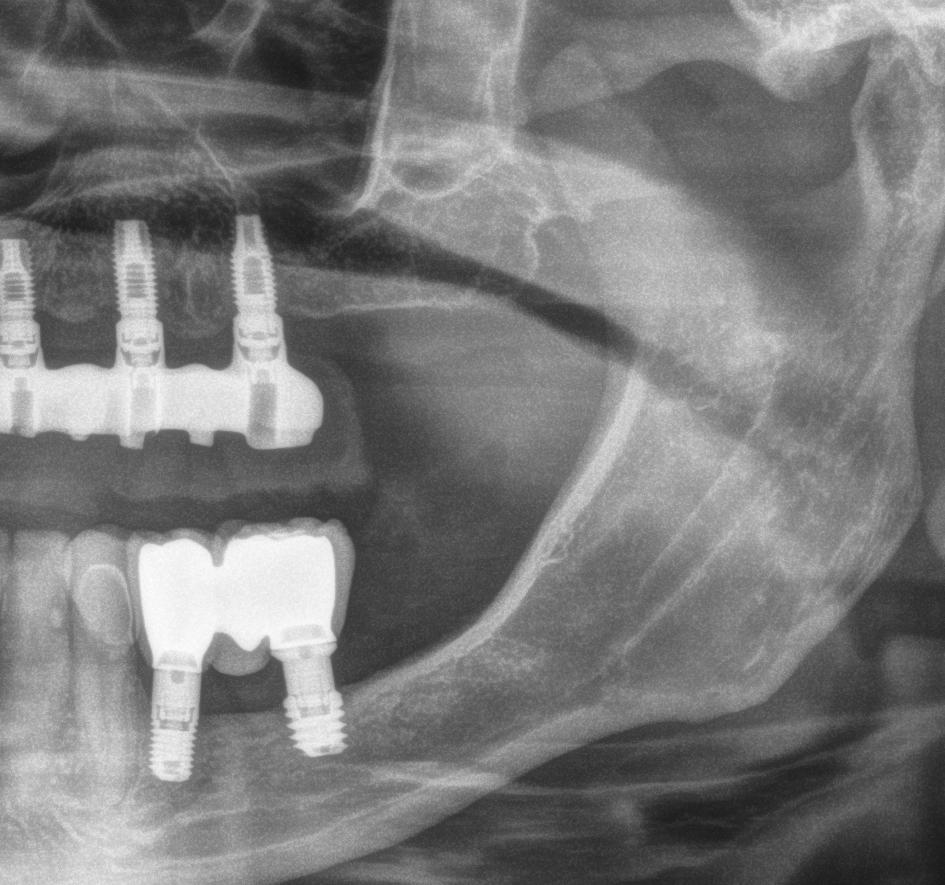

En las piezas 16 y 17 el paciente presentaba restauraciones atornilladas de metalcerámica sobre implantes oseointegrados. Se planificó realizar estas en una fase posterior a la rehabilitación de las piezas dentarias mediante flujo digital con bases de titanio y cuerpos de escaneo.

Finalmente, las restauraciones se cementaron adhesivamente (Figuras 31-35). En las piezas 16 y 17 se realizaron restauraciones cementoatornilladas como última fase de tratamiento. Se recomendó al paciente una férula de protección superior la cual fue elaborada mediante un flujo de trabajo digital (Figura 36)

Planificación de implantes yuxtaóseos y carga inmediata con protocolos Di2gitalArch®️, por el Dr. Luis Cuadrado de Vicente.